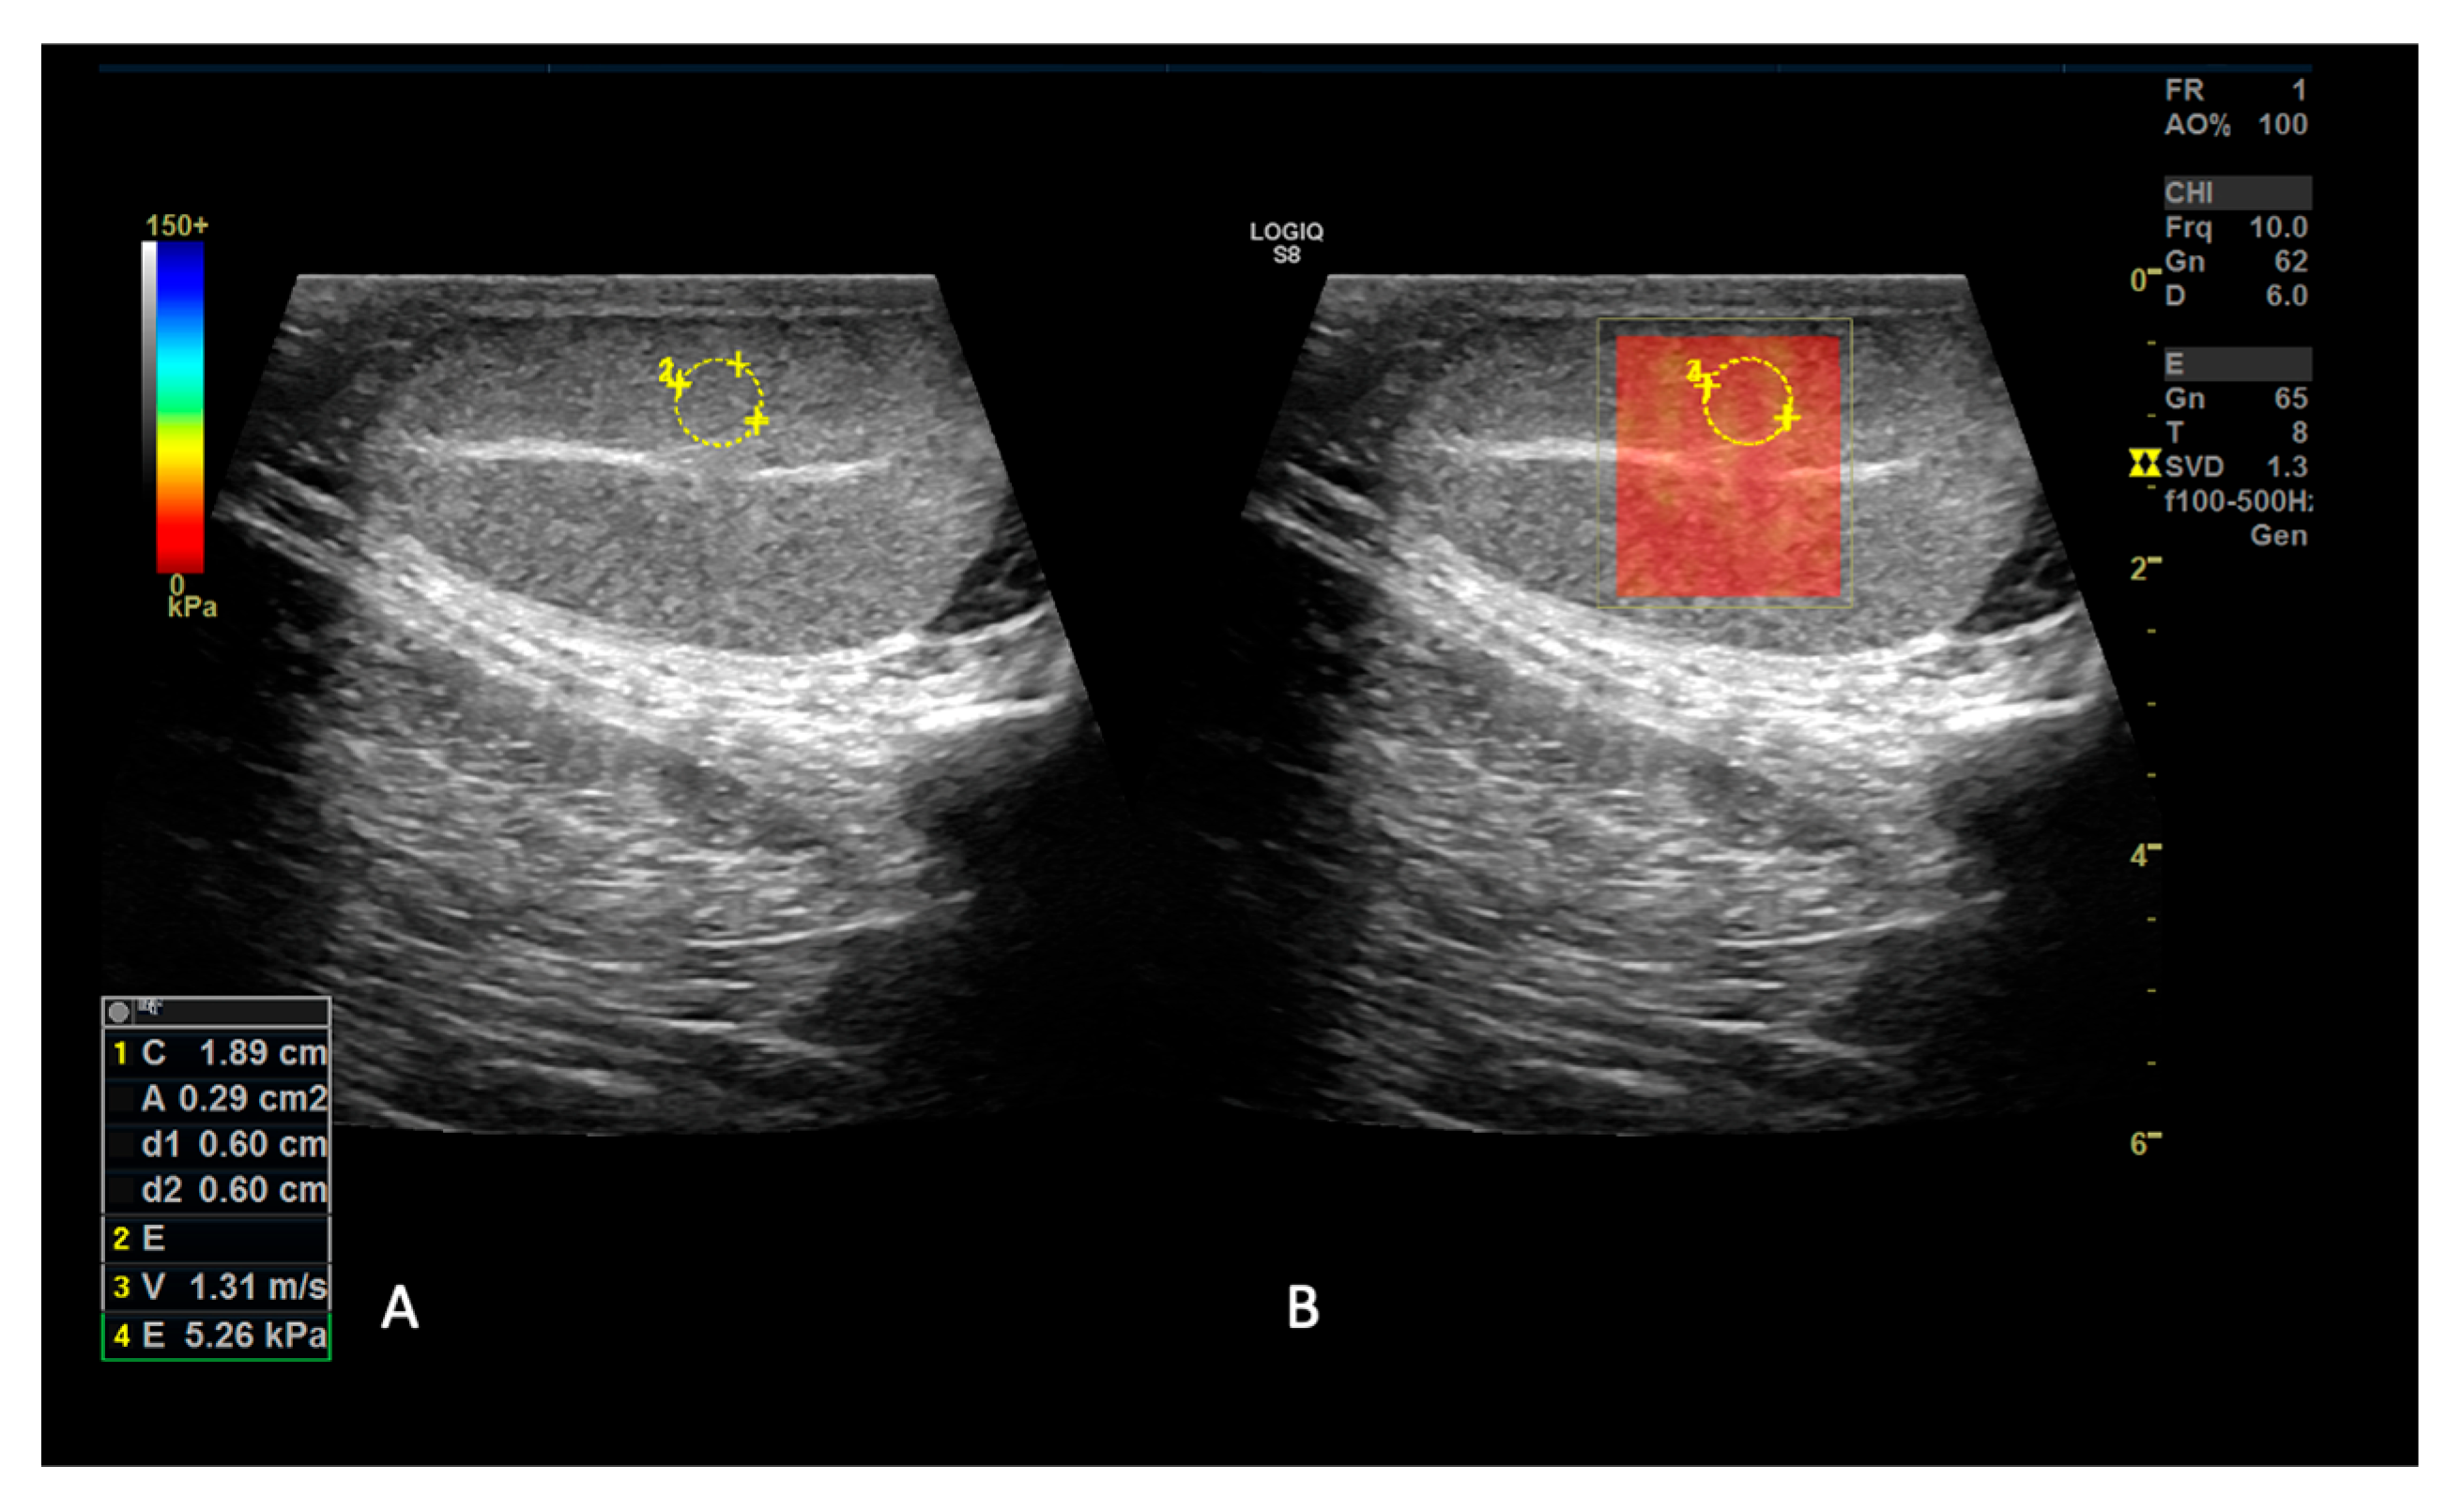

3.3. 2D Shear Wave Elastography

2.1.2. SE and 2D SWE Examination